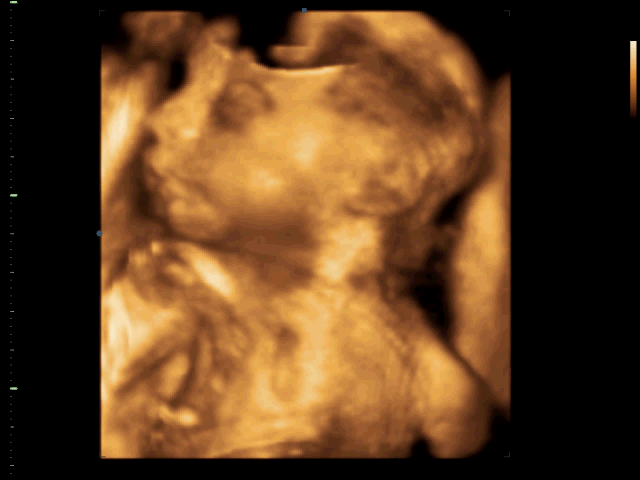

Náš drobek včera na kontrole měl 940g ve 26+5, prý v normě. 3D ultrazvuk nám dělá doktorka na každé kontrole, má ho přímo v ordinaci. Minule se malej schovával, ale teď pózoval jako obvykle, viz obrázek